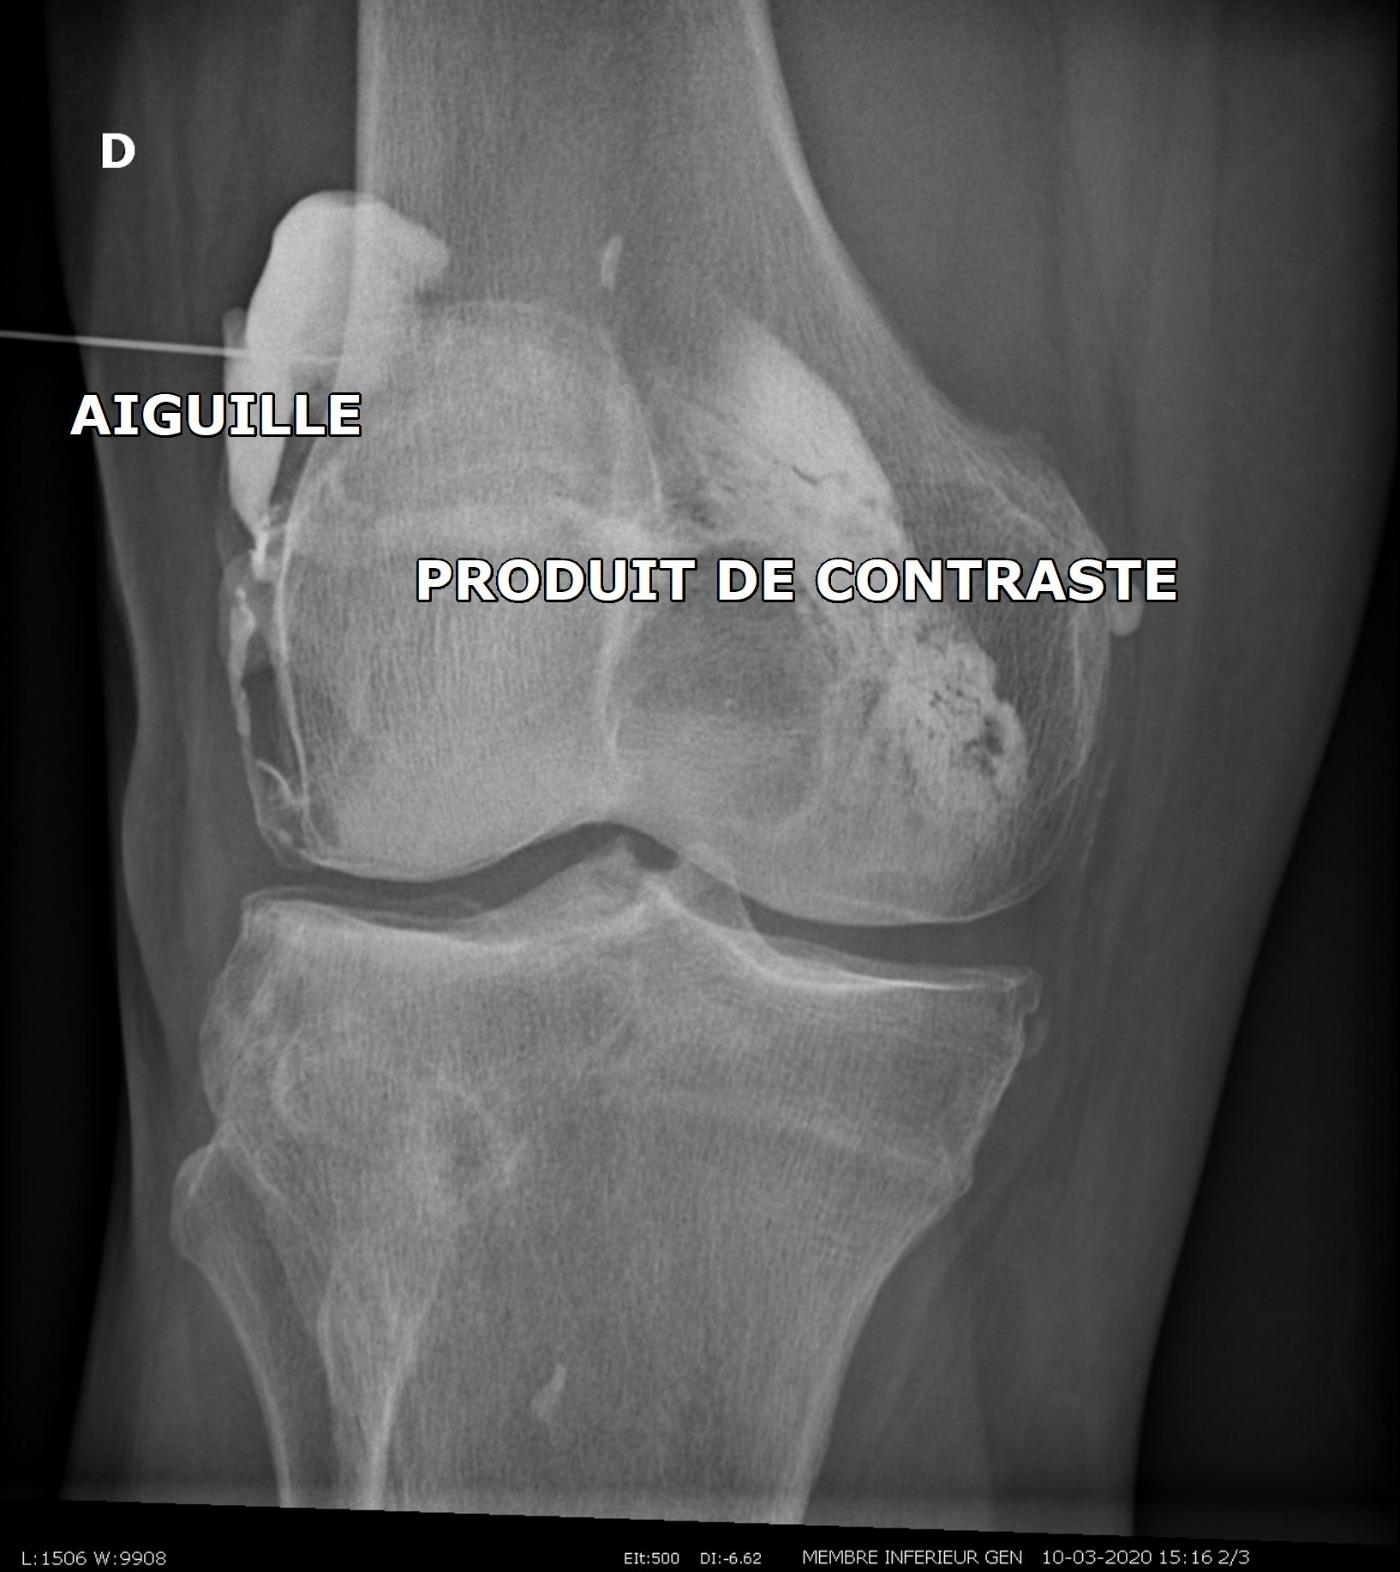

VISCO SUPPLEMENTATION POUR ARTHROSE DU GENOU

L'IRM du genou de cette patient de 64 ans montre un amincissement marqué de l'épaisseur du cartilage du compartiment fémoro tibial externe. Devant la persistance de douleurs invalidantes, son médecin a prescrit une infiltration de corticoïdes et une viscosupplémentation (injection d'acide hyalruonique).

La procédure a été réalisée sous contrôle radiographique.

Il est recommandé d'observer une repos articulaire pendant les 48 heures qui suivent l'injection.